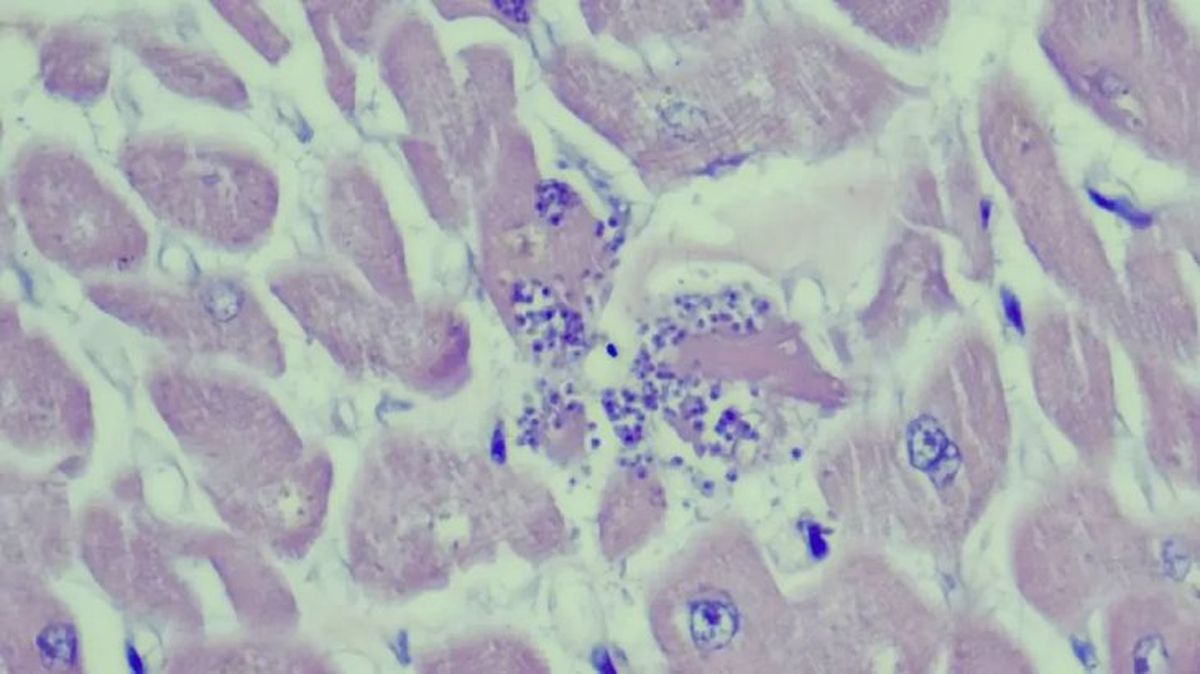

La toxoplasmosis es una parasitosis, es decir, una enfermedad infecciosa causada por un parásito. En este caso el culpable es el Toxoplasma gondii, un protozoo que puede afectar a muchos animales diferentes, humanos incluidos, pero cuyo hospedador definitivo son varias especies de felinos, entre ellas el gato doméstico.

Dentro del cuerpo del gato (solo ahí, nunca en los hospedadores intermedios), el parásito pasa por una fase de reproducción sexual que da lugar a la formación de ooquistes. Podemos considerarlos sacos de huevos que se eliminan a través de las heces y sirven para que el protozoo llegue a nuevos huéspedes cuando estos los ingieren.

• Dentro del cuerpo del gato, la capa protectora que envuelve los quistes se disuelve y los organismos se liberan. Después atraviesan la pared intestinal, se diseminan por todo el cuerpo (ciclo extraintestinal) y se dividen en taquizoitos (son zoitos, u organismos básicos, de multiplicación rápida que forman pseudoquistes en músculos, nervios y otras zonas) y posteriormente bradizoitos (zoitos de multiplicación lenta que principalmente se localizan en el tejido muscular).

Pasadas esas tres semanas, el sistema inmunológico del gato reaccionará y detendrá la formación de taquizoitos y la liberación de ooquistes. Quedarán activos los bradizoitos, formas de replicación lenta del parásito contenidas en quistes repartidos por todo el cuerpo.

En hospedadores intermedios (ganado, pájaros, roedores, etc.) el parásito pasa por el ciclo extraintestinal, pero no por el enteroepitelial. Es decir, se generan bradizoitos enquistados por el cuerpo, pero no ooquistes.